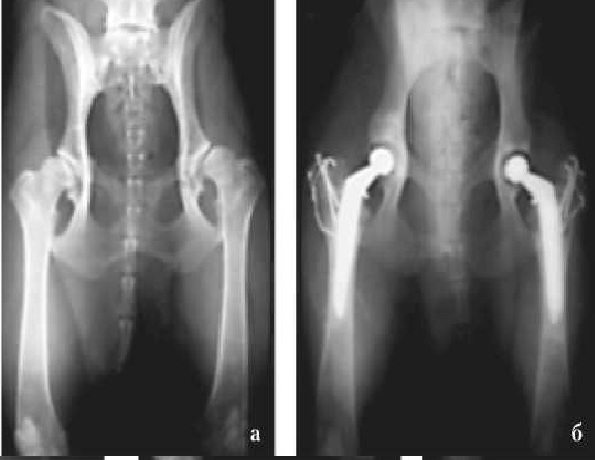

Во второй группе животных средний срок службы ЭП составил 1569 сут (от 798 до 2127) (рис. 3). АН развилась в 2 из 18 случаев (11,1 %). Появление хромоты и зоны лизиса костной ткани вокруг цементной мантии ЭП отмечали в среднем через 520 сут (336 и 704). Этим животным операция была выполнена повторно.

Рис. 3. Рентгенограмма. Тотальное эндопротезирование тазобедренных суставов с тяжелой степенью дисплазии (а) эндопротезами MATHYS (б)

Рис. 4. Рентгенограмма таза в I и III позиции. Дисплазия ТБС тяжелой степени (а). Тотальное эндопротезирование ТБС с пластикой аутокостью и реконструктивной пластиной края суставной впадины (б)